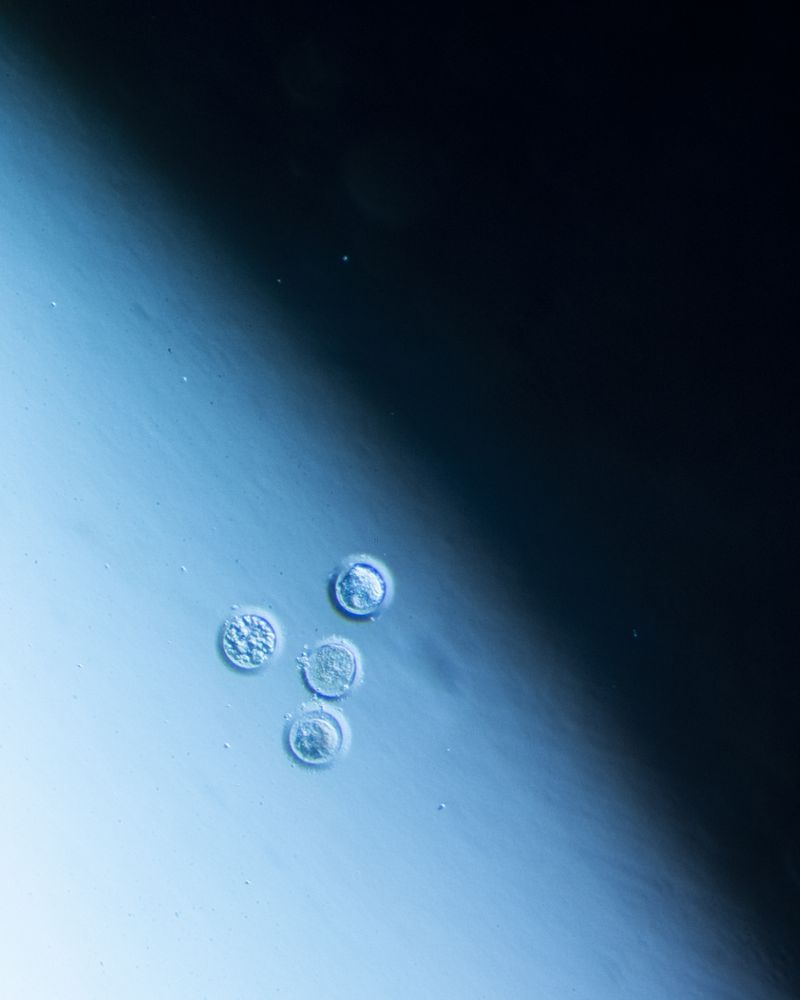

At the moment of fertilization, the egg releases chemical signals that attract the ideal spermatozoid, the most compatible, to its center. Over the next two weeks, by some inexplicable chance, it’s possible that the fertilized egg will divide into two exactly equal zygotes, and it’s at that moment that the gestation of monozygotic twins will begin, two beings with the same DNA chain and genetic information.

Las dos hebras (The Two Strands) seeks to understand, through history and metaphor, the other who is me, returning to that miniscule moment that gives way to my origin and that of my twin. I try to understand, decipher, and imagine it. My search has centered on the study of genetic history from the time of Pythagoras and that of the mystical sperm that gathers secret instructions on its journey throughout the body; on Aristotle who sustained that hereditary information was not found in the matter but in the message, like that of the drawings of the beaks of mockingbirds and Darwin’s tree of life. I have spent a great deal of time considering these events, recreating in my mind the human process for discovering oneself. I was accompanied by the work of Mendel, who obsessively cultivated and selected almost 400,000 seeds, hoping to find those that would produce identical descendants. I investigated the wet lab of Rosalind Franklin, British chemist and crystallographer, her life dedicated to science, and her discoveries that went unrecognized. Rosalind worked on deciphering the codes of nature, of crystals, and of invisible structures. She was the first to contemplate the image of an enigmatic molecule capable of containing hereditary information, what seemed to be the secret of life.

I traced the notes in Rosalind Franklin’s diaries, which review the power of images and how those images offer us answers. I used the answers from scientists from the second half of the twentieth century in regards to the nature of DNA, the molecule with 23 angstroms, as a metaphor, a bridge or a pathway in order to imagine and reflect on the nature of monozygotic twins. “DNA is made up of two interlocking chains arranged like the steps of a spiral staircase. The two strands contain the same information, except that they are in a complimentary position: each one is a reflection of the other. The most transcendental biological objects always appear in pairs.”1

In Las dos hebras, I combined archival images from the study of genetics, diagnostic images of my genes and those of my twin, photographs of monozygotic twins, microscopic photographs that were taken in science and fertility labs, and images with poetic symbols that, as a whole, seek to establish contact with other people, whether twins or not, who may arrive at a place to question what in this alphabet, reflexive code, or mirrored code makes us human.